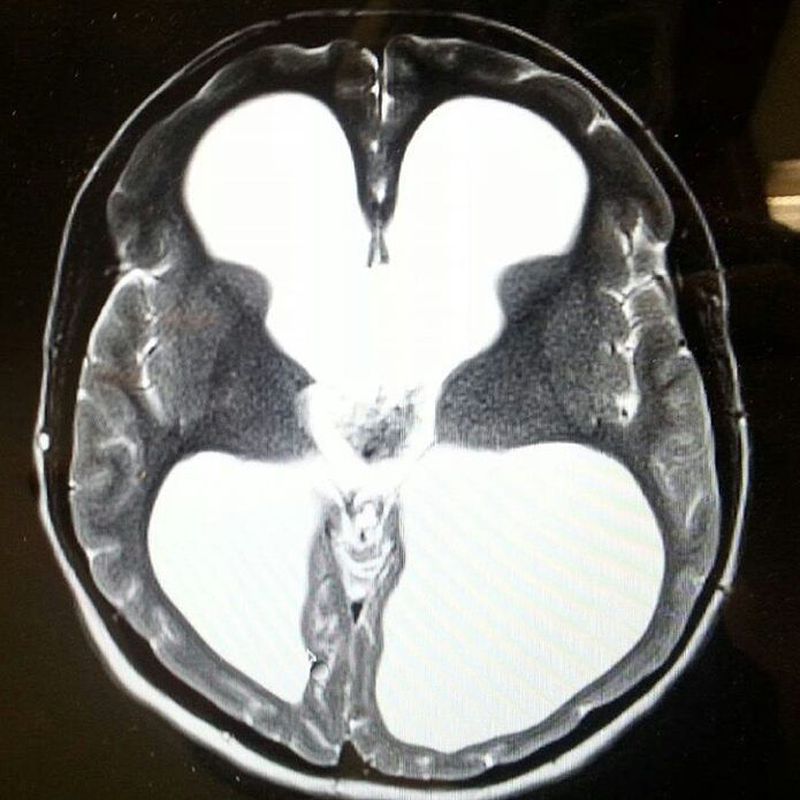

This is the brain of someone who is as normal as me and you, it shows Congenital Hydrocephalus: congenital disease characterized by abnormal accumulation of cerebrospinal fluid in the brain due to obstruction in the CSF rainage. This is the case of 21 years old female who was born with this malformation and got treated surgically with ventricular shunt to surpass the obstruction, whats remarkable here is that she has full cognitive function and do really good in school which shows how elastic is the brain and it can learn lost functions specially in the first years of life. follow us for more !